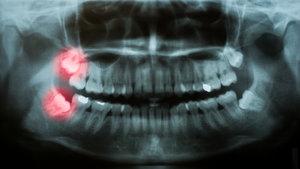

- Wisdom teeth

Surgical extractions involve teeth that have not fully erupted from the gums. This often occurs when there is not enough space for the tooth or it is growing in at an angle. This condition, known as impaction, often causes pain and jaw discomfort. Removing your tooth can dramatically improve your comfort.